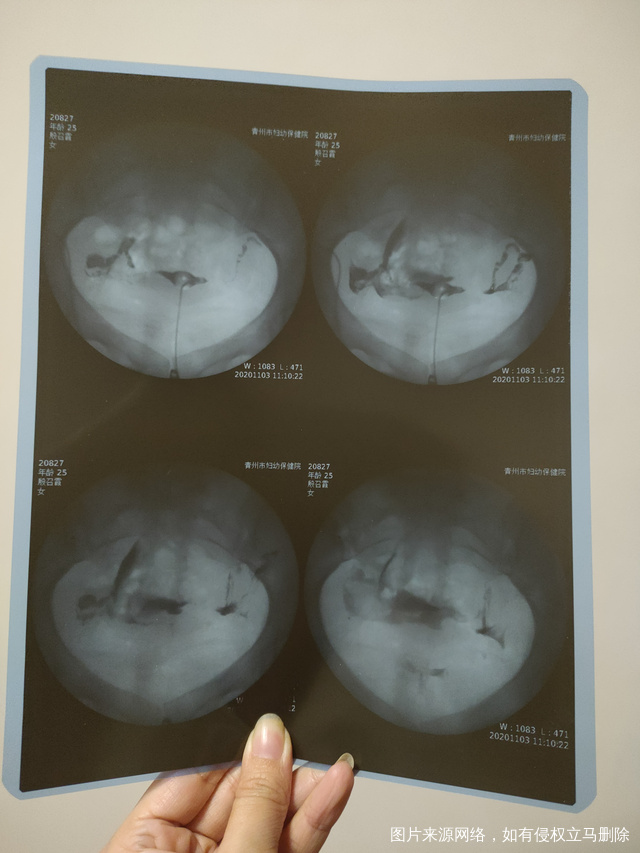

做完输卵管造影第六天了小腹还是感觉沉甸甸的如

可以热敷腹部,如果有发热,腹痛加剧,白带量多,有异味,随时就医